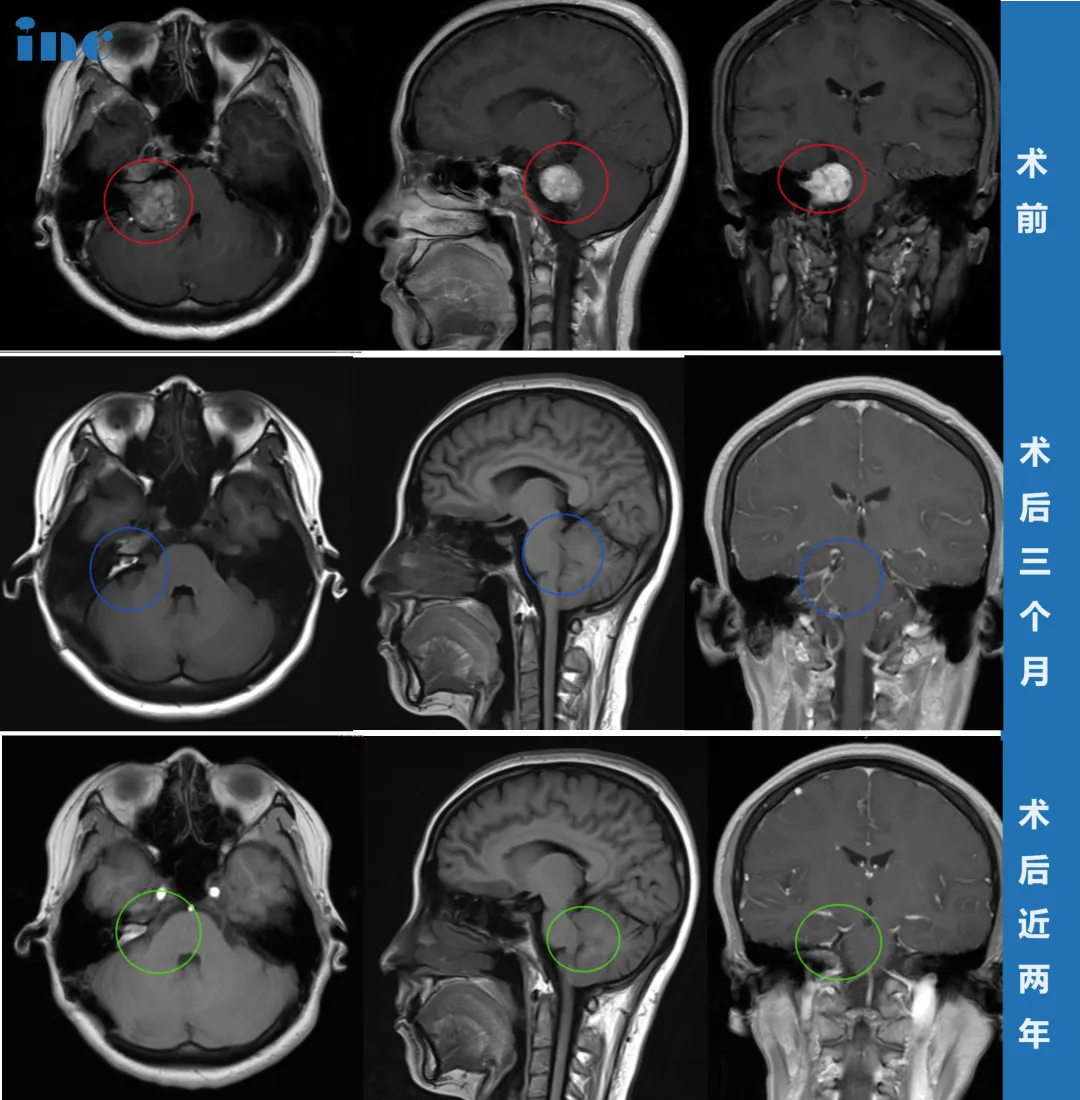

这次她直接做了头颅核磁,结果让她如遭雷击——右侧桥小脑角区(CPA区)前庭神经鞘瘤(即听神经瘤),最大直径约35mm(含内听道部分),已压迫脑干、桥脑及右侧桥臂,四脑室也变了形。她翻出2019年的CT问医生,得到的答案是“当时确实无法发现”。

手术当天的细节,让李女士格外安心:没有剃全头,只剔除手术部位的头发;麻醉安全到位,全程监测生命体征;采用半坐位体位,确保术中视野清晰。巴教授根据肿瘤位置和形态,制定了个体化手术入路,在神经电生理监测和MRI辅助下,于显微镜下精准切除了全部肿瘤,全程保护了神经功能和重要脑组织。

术后当天,李女士就拔除了气管插管,能完全自主呼吸。复查CT显示正常,没有脑出血等并发症,随后转入普通病房康复。

出院时,她全身状态已恢复良好:术前的右侧面部麻木等症状明显好转,虽然术后由于手术水肿出现了短暂的面瘫,但是在她的积极康复锻炼下,术后2个月基本恢复,术后半年时恢复良好,术后近2年没有复发。